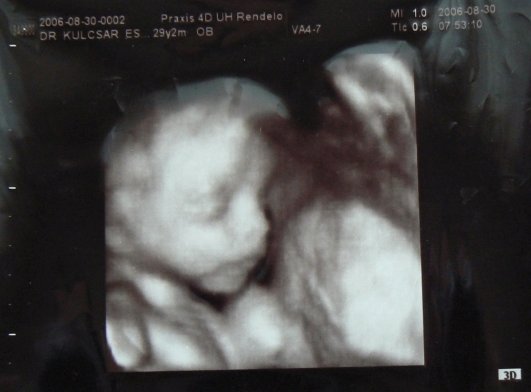

Várom a tegnapi uh eredményét

Meg képet meg mindent